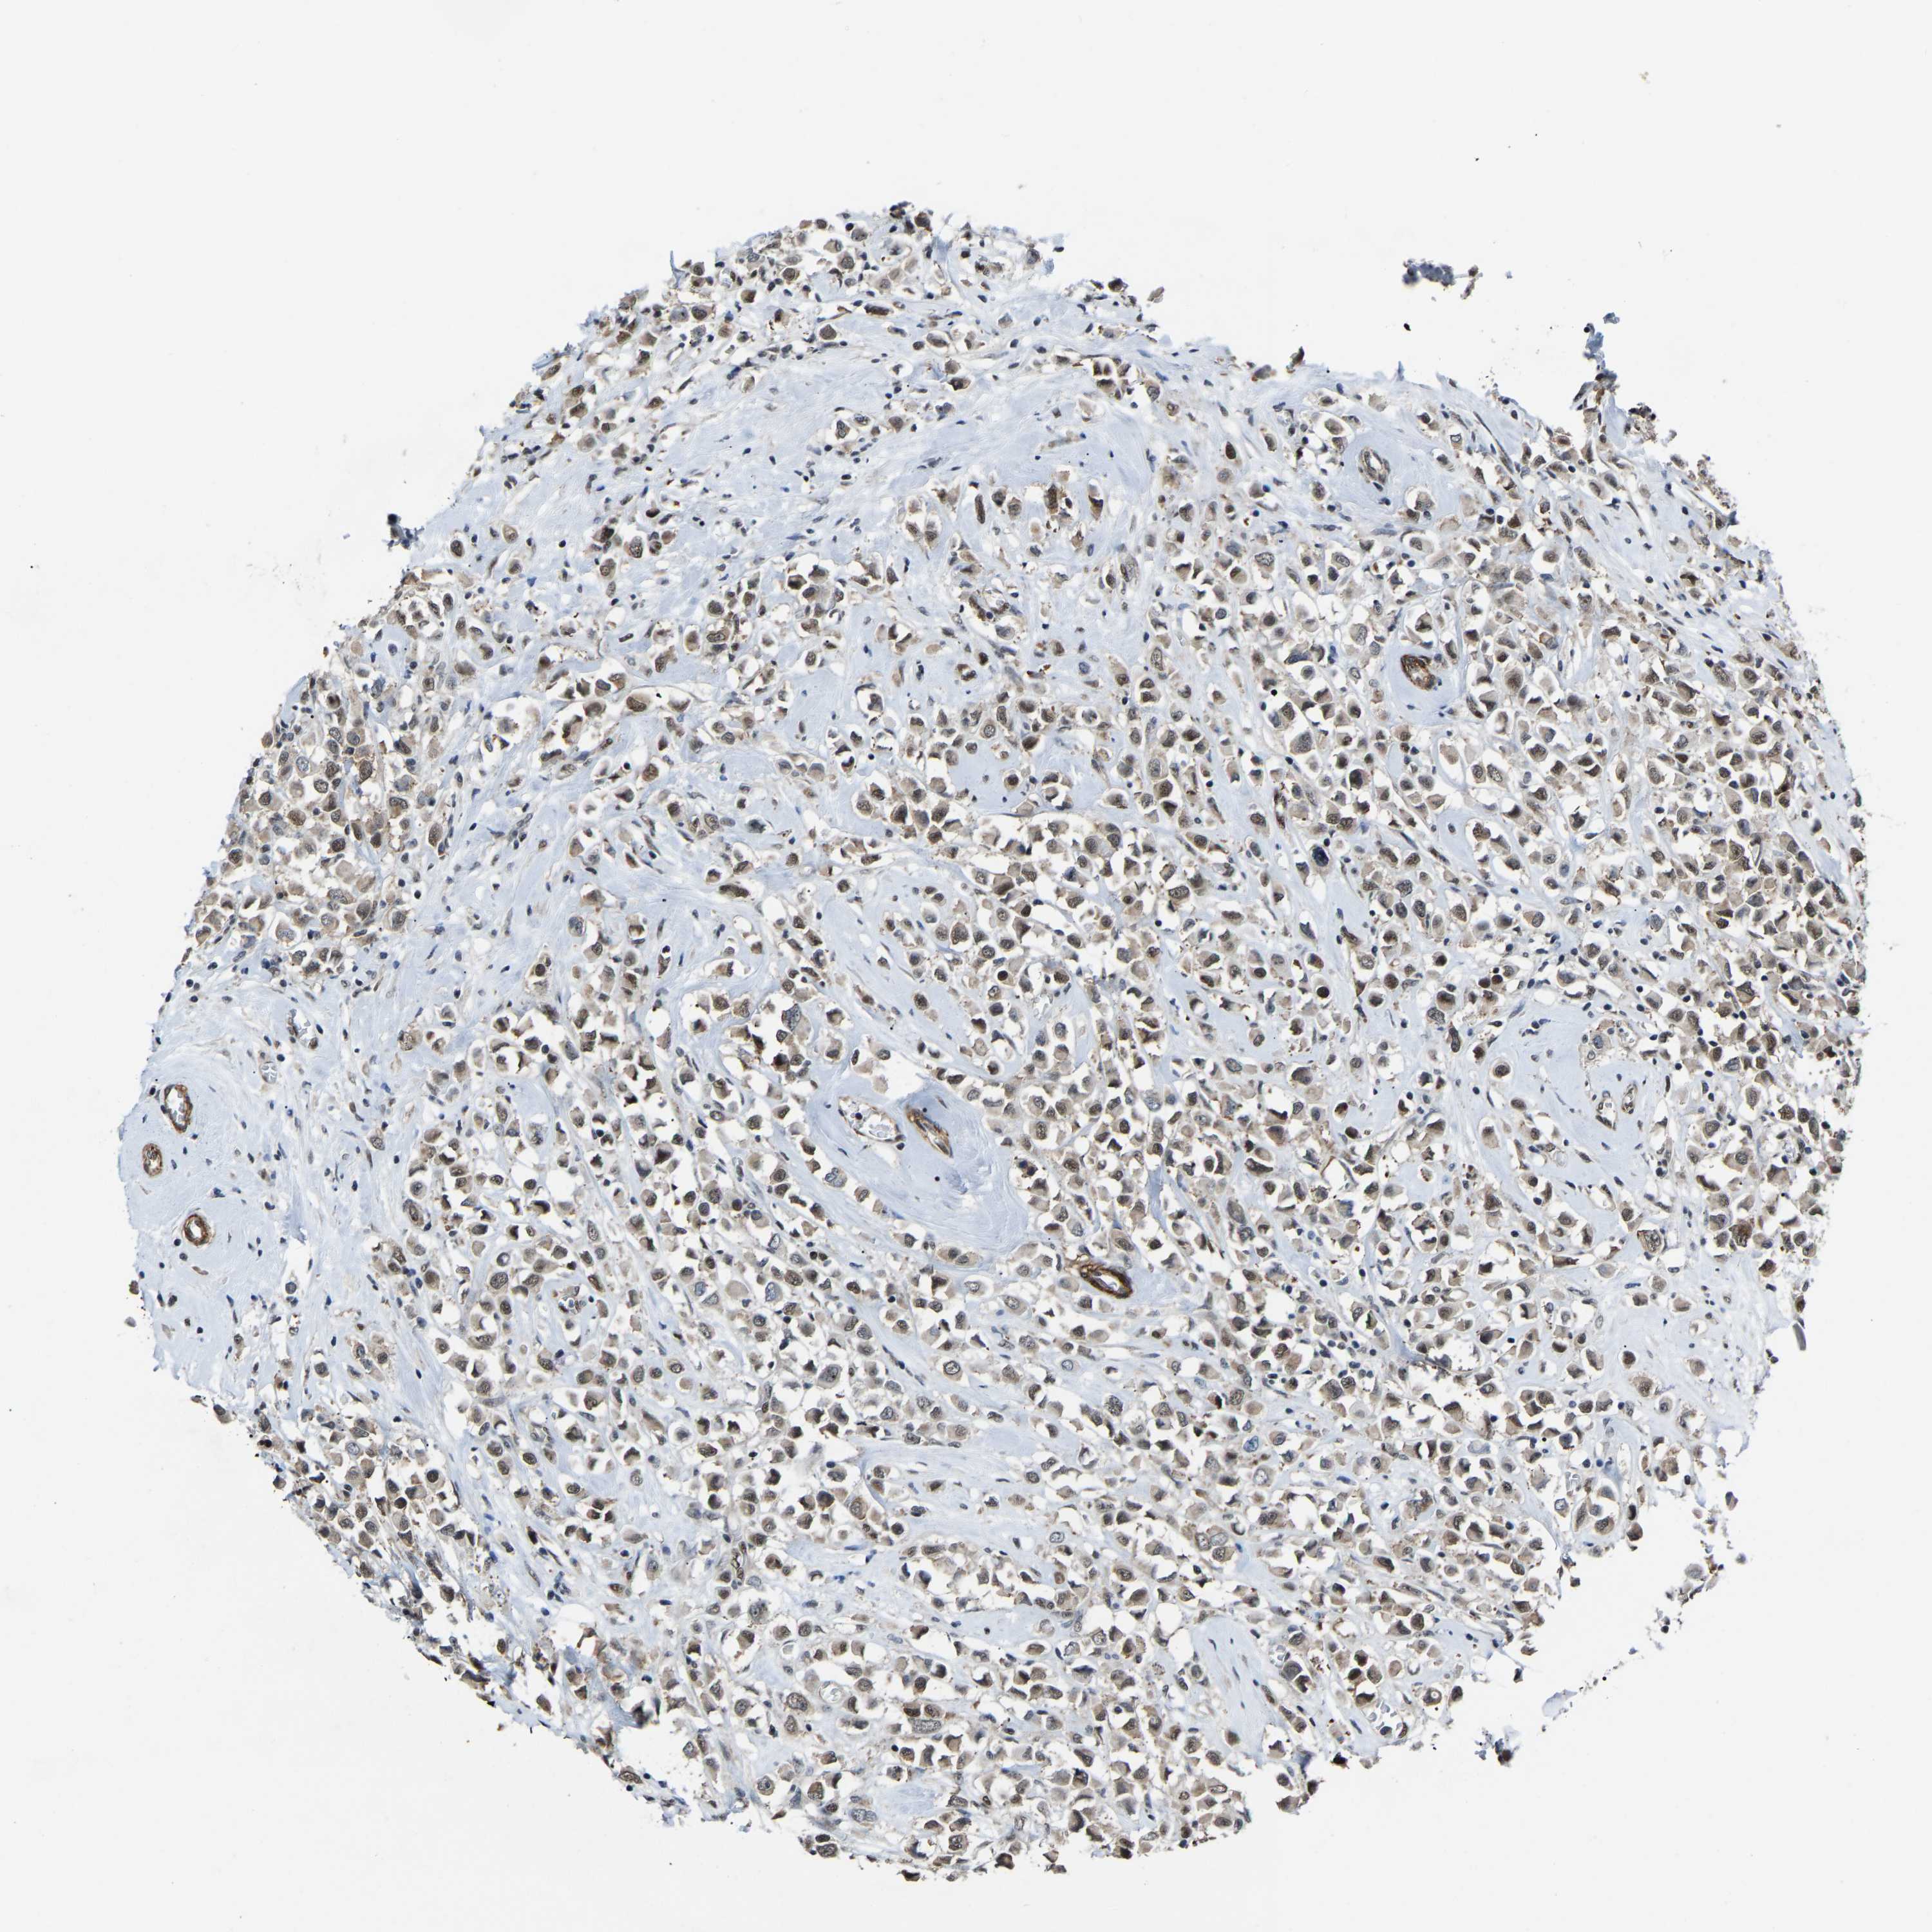

CANCER BREAST CANCER Show tissue menu

BRCA TCGA BRCA VALIDATION PROTEIN EXPRESSION